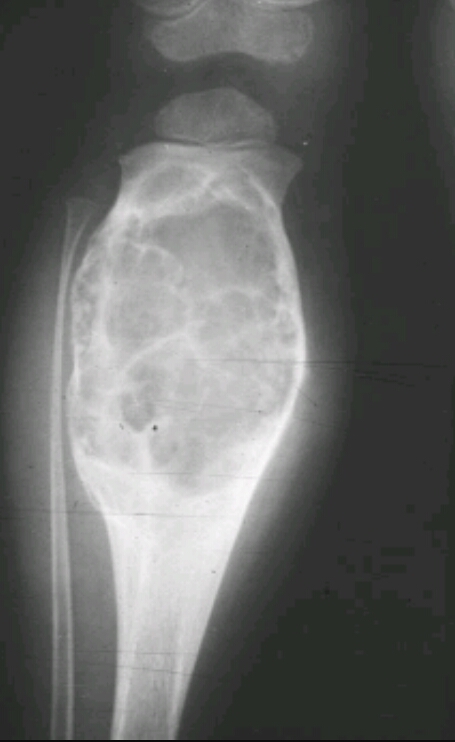

Patient is a 60 year old male has and has been complaining of pain, unexplained weight loss and recurrent respiratory infections. You take this xray and labs. Elevated ESR and M spike. What are the findings? Diagnosis?

Osteoporosis/osteopenia, soap bubble appearance

Multiple myeloma